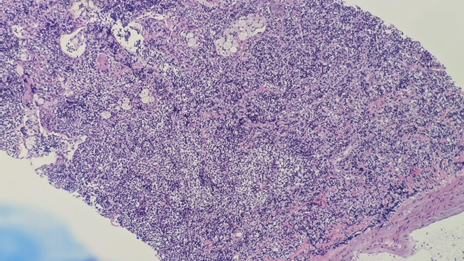

Pulmonology | Nov 24, 2025

A Silent Intruder: Case Report of Primary Pulmonary Follicular Lymphoma Mimicking Infectious Lung Disease in a Patient with Autoimmune Comorbidities

Primary pulmonary follicular lymphoma (PPFL) is an exceptionally rare subtype of non-Hodgkin lymphoma that arises within the lung parenchyma without...Read More